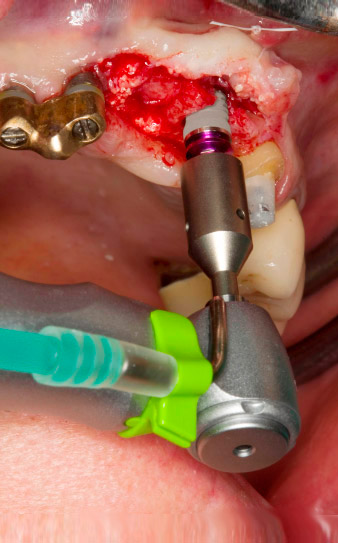

pilot drilling is performed with the new Implantmed and the WS-56 L contra-angle handpiece

Fig. 2: Two months later the pilot drilling is performed with the new Implantmed and the WS-56 L contra-angle handpiece (programme P1, ratio 1:1). The cooling is performed via the spray tube positioned on the left (for right-handed users).